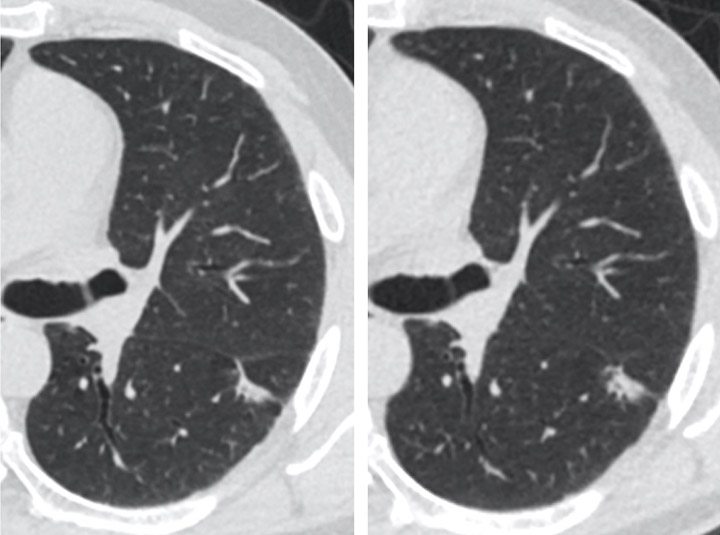

Small peripheral lung cancer seen on the baseline screening CT examination (left)

and on a 3-month follow-up CT (right) within the CT lung cancer screening program.

Because the original nodule had grown on follow-up, it was resected via

minimally-invasive surgery. No additional therapy was needed, the patient is doing well.